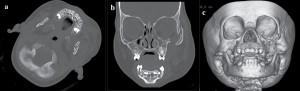

- Перелом скуловой кости

- Rg перелома скуловой кости